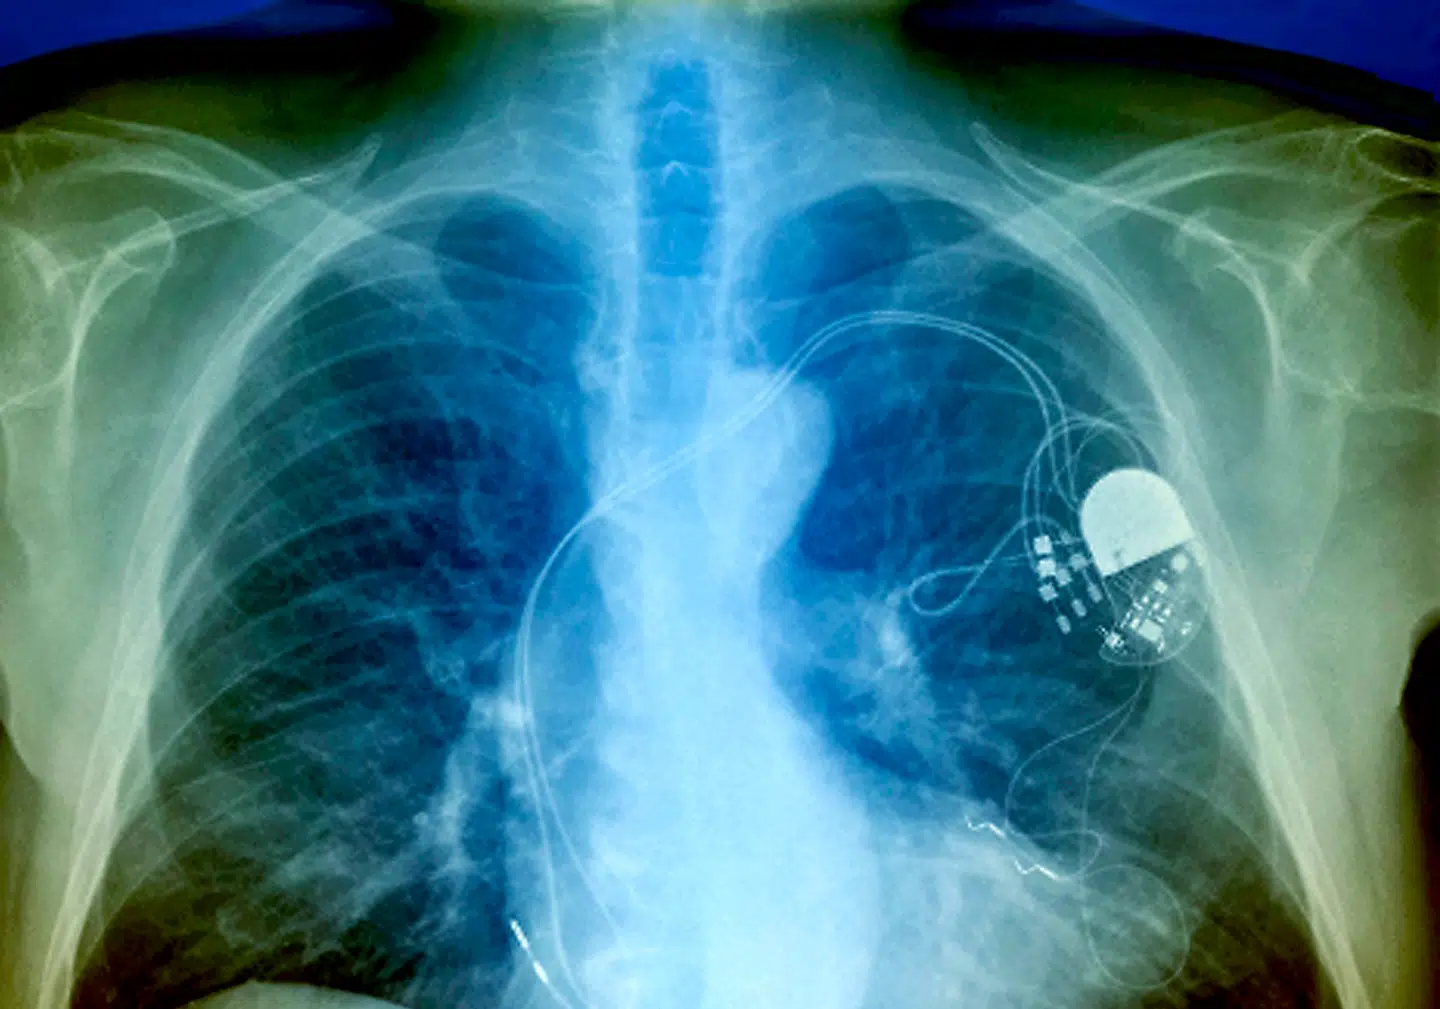

Det er et »rødt flag«, som vedrører de hjertepatienter, som har pacemaker eller indopereret hjertestarter (ICD). Det skriver Ingeniøren.

På baggrund af studiet peges der på flere mulige konsekvenser: Pacemakeren kan stoppe med at virke i en periode, og de indopererede hjertestartere kan blive forvirret til at tro, at der er noget galt med patientens hjerterytme og give et unødigt stød.